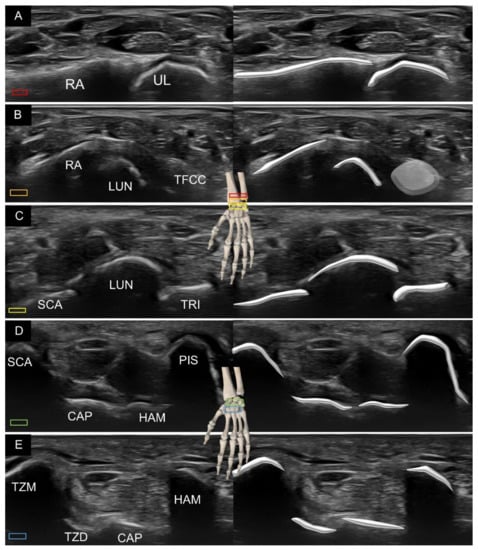

2. Sonoanatomy of Carpal Bones

3. Sonoanatomy of Volar Extrinsic Carpal Ligaments

3.1. Attachment to the Capitate

3.2. Attachment to the Lunate

3.3. Attachment to the Triquetrum

4. Sonoanatomy of Volar Intrinsic Carpal Ligaments

5. Sonoanatomy of Dorsal Extrinsic Carpal Ligaments

Attachment to the Triquetrum

6. Sonoanatomy of Dorsal Intrinsic Carpal Ligaments

7. Sonoanatomy of Wrist Collateral Ligaments